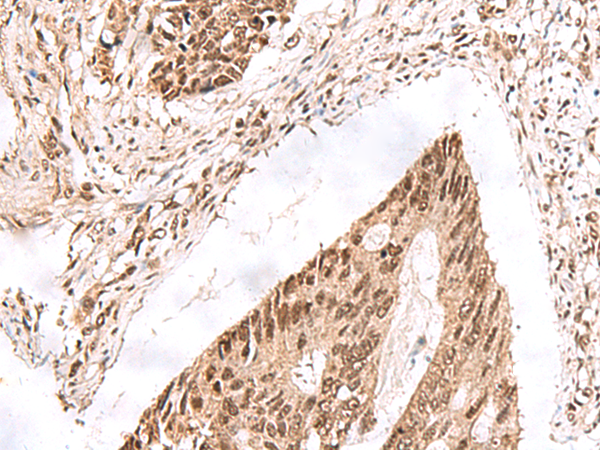

IHC 1/25-1/100 Human,Mouse,Rat

The EXD2 antibody enables detection and analysis of EXD2 expression, localization, and protein interactions in various models. It is utilized in techniques like Western blotting, immunofluorescence, and immunoprecipitation to explore EXD2's molecular mechanisms in DNA repair, replication stress response, and mitochondrial RNA processing. Research using this antibody has helped clarify EXD2's dual role in maintaining genome integrity and its tissue-specific expression patterns. Ongoing studies aim to define its therapeutic potential as a biomarker or target in cancer and diseases linked to DNA repair deficiencies.